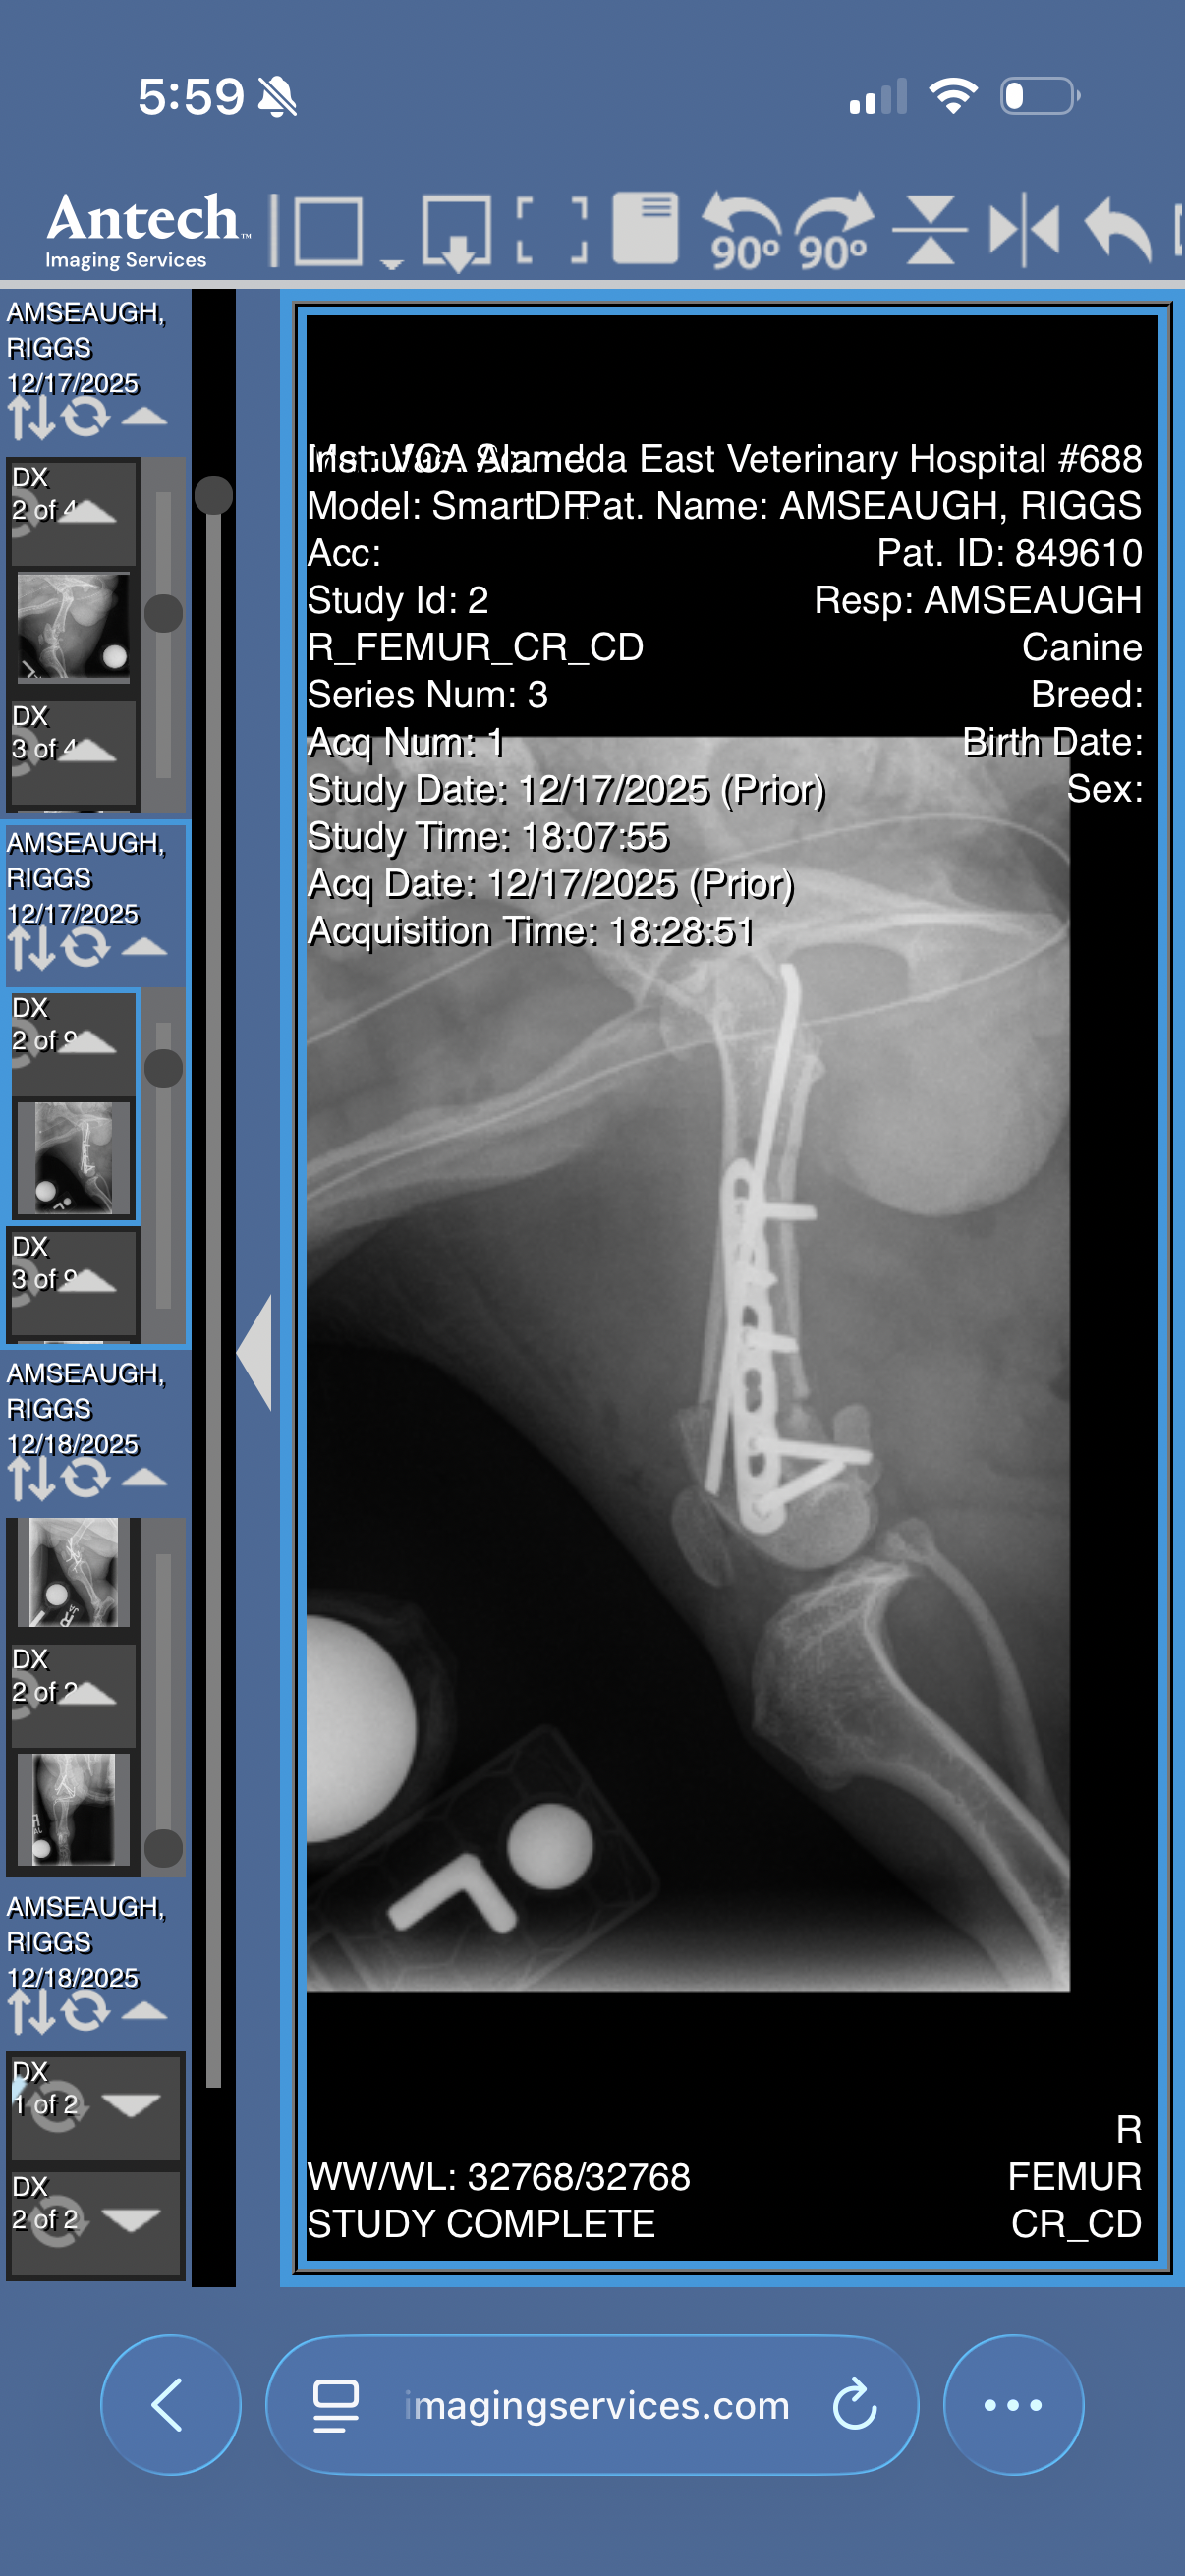

On Monday night, Riggs was hit by a car. The accident left him with two broken back legs and bruising in his ribs and lungs. Seeing him in pain has been heartbreaking, and I’m doing everything I can to make sure he gets the care he needs. The veterinarians have told me that Riggs will need orthopedic surgery to have any chance at a healthy, happy life. The procedure is complex and costly, but it’s his best hope for a full recovery.